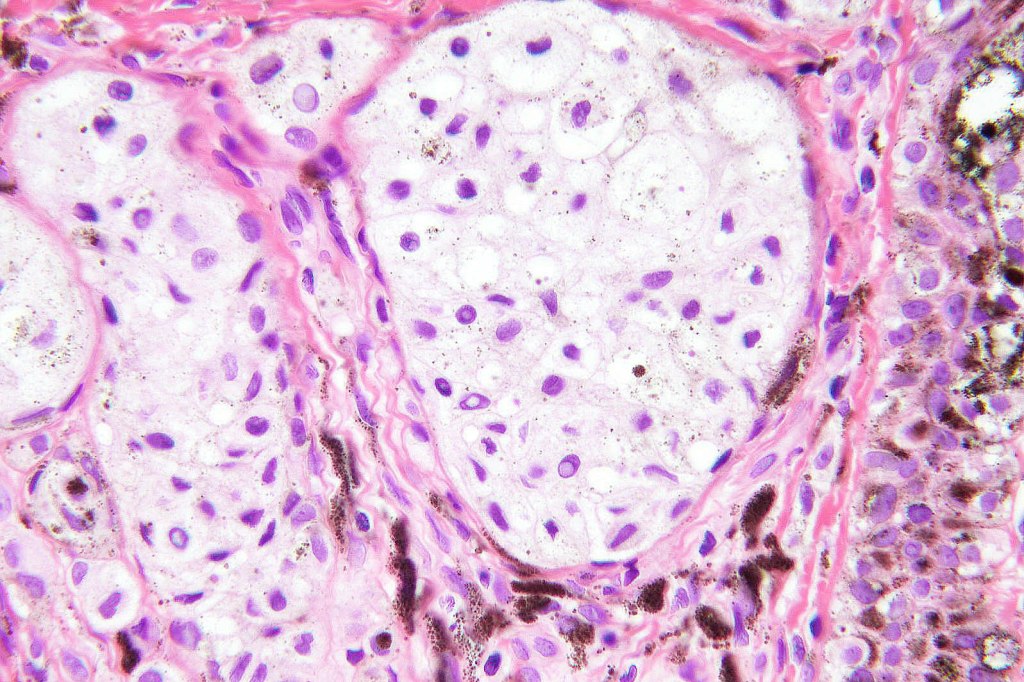

•May affect the tumor in part or whole

•Enlarged cells with copious eosinophilic, foamy or clear cytoplasm (some authors include melanoma with clear cell change in the same category)

•Variable pigmentation

•Nuclei vesicular or hyperchromatic

•Pleomorphism is not generally marked and indeed can be very subtle

•DPAS granules